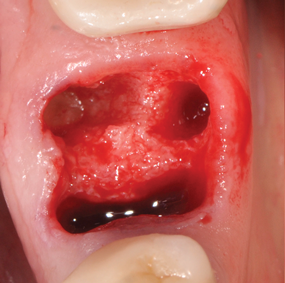

(6.) Careful extraction should be emphasized to maintain as much bone as possible, especially for immediate implants replacing multirooted teeth.

Figure 6